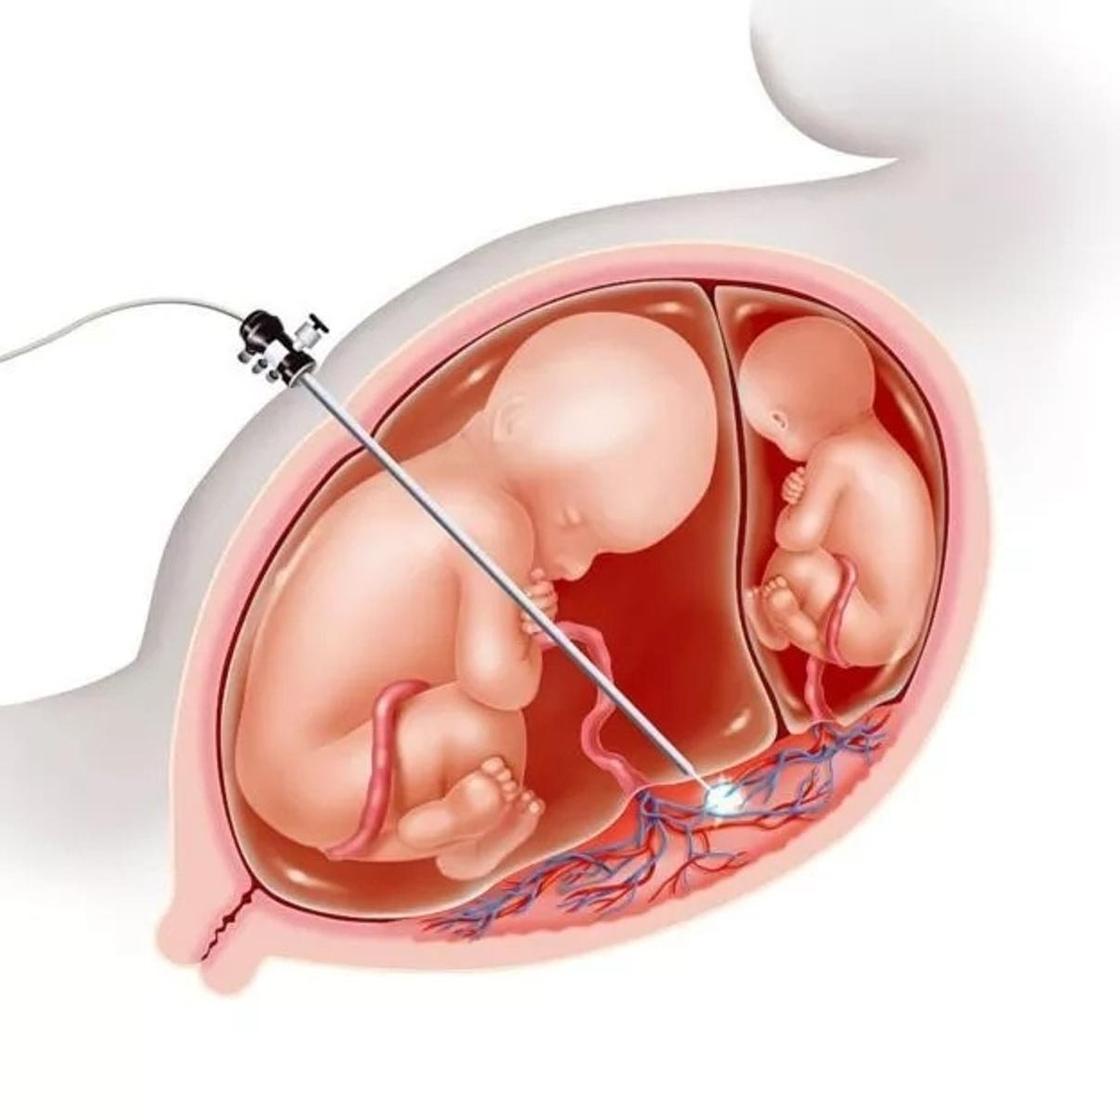

Околоплодный пузырь и плацента: структура и функции